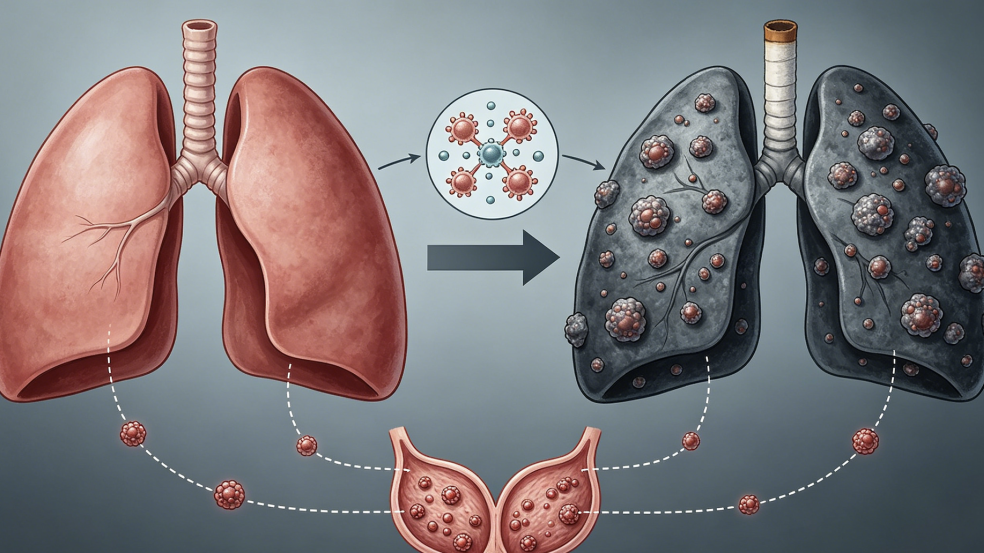

提到吸烟的危害,大多数人第一反应就是肺癌,这个认知没有错。长期吸烟确实是肺癌最主要的危险因素,烟草燃烧产生的焦油、尼古丁和多种致癌物,会持续刺激支气管和肺泡黏膜,导致细胞异常增生。临床上,很多肺癌患者在确诊时,烟龄往往已经超过二十年。

但如果我们只把吸烟和肺癌画等号,就大大低估了它的破坏力。烟草对身体的伤害是全身性的,几乎没有一个器官能幸免。

除了肺癌,吸烟还会引发慢性阻塞性肺疾病,也就是常说的慢阻肺。这种病早期表现为长期咳嗽、咳痰,活动后气短,很多人误以为是年纪大了或者感冒后遗症,不以为意。但随着病情进展,患者会逐渐出现呼吸困难,甚至走几步路就喘不上气,生活质量严重下降。慢阻肺一旦形成,肺功能损伤往往是不可逆的,戒烟是延缓病情最有效的手段。

从临床观察来看,长期吸烟的人群出现肺结节的概率确实更高。虽然并非所有肺结节都是恶性的,但吸烟会让良性结节向恶性转化的风险增加。这是因为烟草中的致癌物持续刺激肺组织,导致局部炎症反应和细胞修复异常,久而久之,就可能形成结节,甚至发展为肿瘤。

除了肺结节,吸烟对全身免疫系统的影响也不容忽视。免疫力下降后,身体对各种异常细胞的监控能力减弱,甲状腺、乳腺等部位的结节问题也可能随之增多。